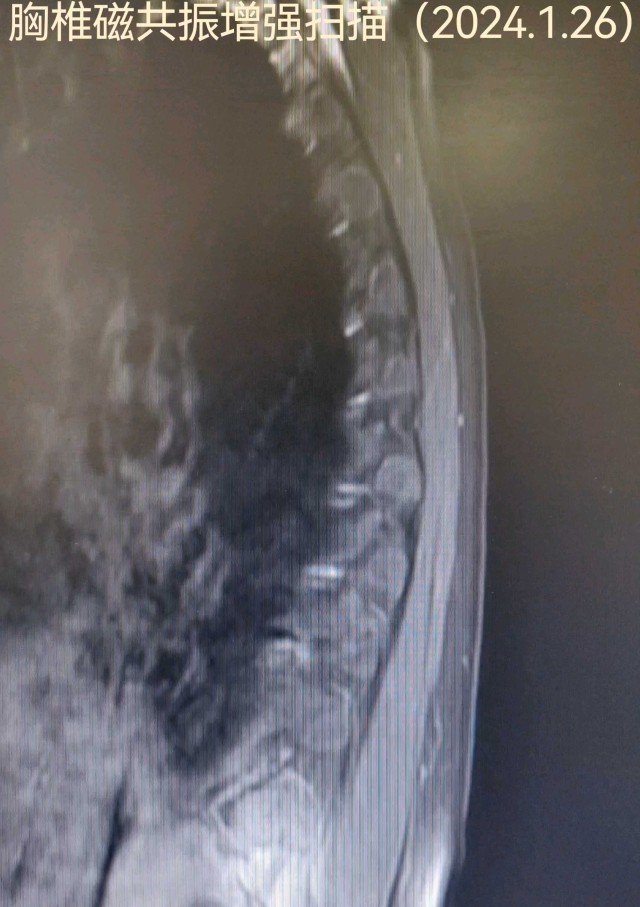

白某某,女性,73岁,2024年01月09日入院。主诉:进展性双下肢无力15天现病史:15天前(12月26日7:00)无明显诱因突发双下肢无力,可缓慢行走,(12月26日9:00)渐进行性加重,双下肢抬离床面困难,不能行走,伴双下肢感觉障碍,小便困难及大便失禁,持续性,无头痛、眩晕、恶心、呕吐,无意识丧失、肢体抽搐、口吐白沫、双眼凝视,偶有口角流涎,无言语含糊、饮水呛咳、吞咽困难。立即就诊于当地县人民医院,因起病急,症状重,病情进展快,双下肢感觉障碍,尿便障碍,短时间内诊断困难,当天转诊于某大学附属医院神经外科,按双下肢无力待查:胸髓缺血诊治后好转,双下肢较前有力,可借助外物缓慢挪步,行走不稳

coverplay

病例 · 319 浏览 · 4 讨论